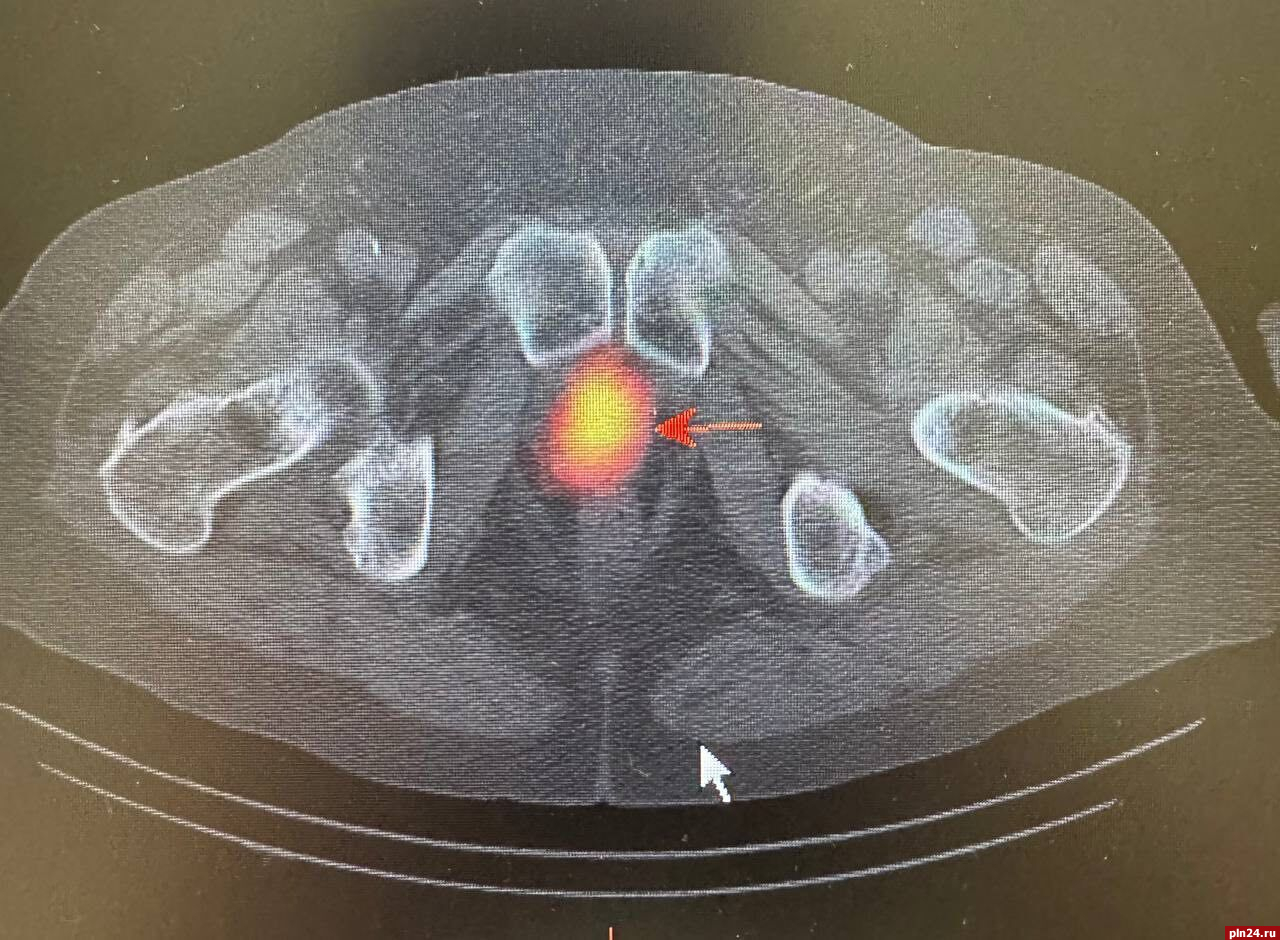

Для уточнения диагноза и получения более детальной информации о состоянии лимфатических узлов была назначена радионуклидная диагностика. Этот метод позволил более точно определить наличие злокачественного опухолевого процесса в предстательной железе, а также подтвердить метастатическое поражение ранее выявленных лимфатических узлов в грудной клетке. Кроме того, радионуклидное исследование показало активное накопление технеция ПСМА в парааортальных лимфатических узлах с обеих сторон.

При этом важно отметить, что на компьютерной томографии не было явных структурных изменений, что затрудняло оценку их состояния и возможности метастазирования, уточнили в министерстве.